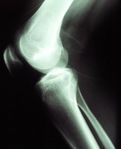

الركبة Knee مفصل تلتقي عنده عظمة الفخذ مع العظمة الكبيرة للساق السفلى. وتتحرك الركبة، مثل المفصّلة، ويمكنها أن تدور وتتحرك قليلاً من جهة إلى أخرى. والركبة أكثر قابلية للتلف من معظم المفاصل، إذ إنّها عُرضة لضغوط كبيرة عند النشاط الزائد. ومعظم إصابات الركبة التي تحدث في كرة القدم والرياضات الأخرى تنتج من التواء المفصل.

والرضفة (غطاء الركبة) عظمة مسطحة مثلثة صغيرة في مقدمة المفصل. وهي ليست موصولة بطريقة مباشرة مع أية عظمة أخرى. وتعمل أربطة عظمية على بقائها في مكانها.

وتتصل عظمة الفخذ والظنبوب (عظمة الساق السفلى الكبيرة) بثلاث طرق هي : 1 – بالأربطة (أنسجة قوية شبيهة بالوتر)، 2 – بالعضلات، 3 - بمحفظة زليلية. وتحيط المحفظة الزليلية بالمفصل. وأربطة الركبة هي الموصلات الأقوى بين عظمة الفخذ والظنبوب. وهذه الأربطة تمنع العظمات من التزحزح عن مكانها.